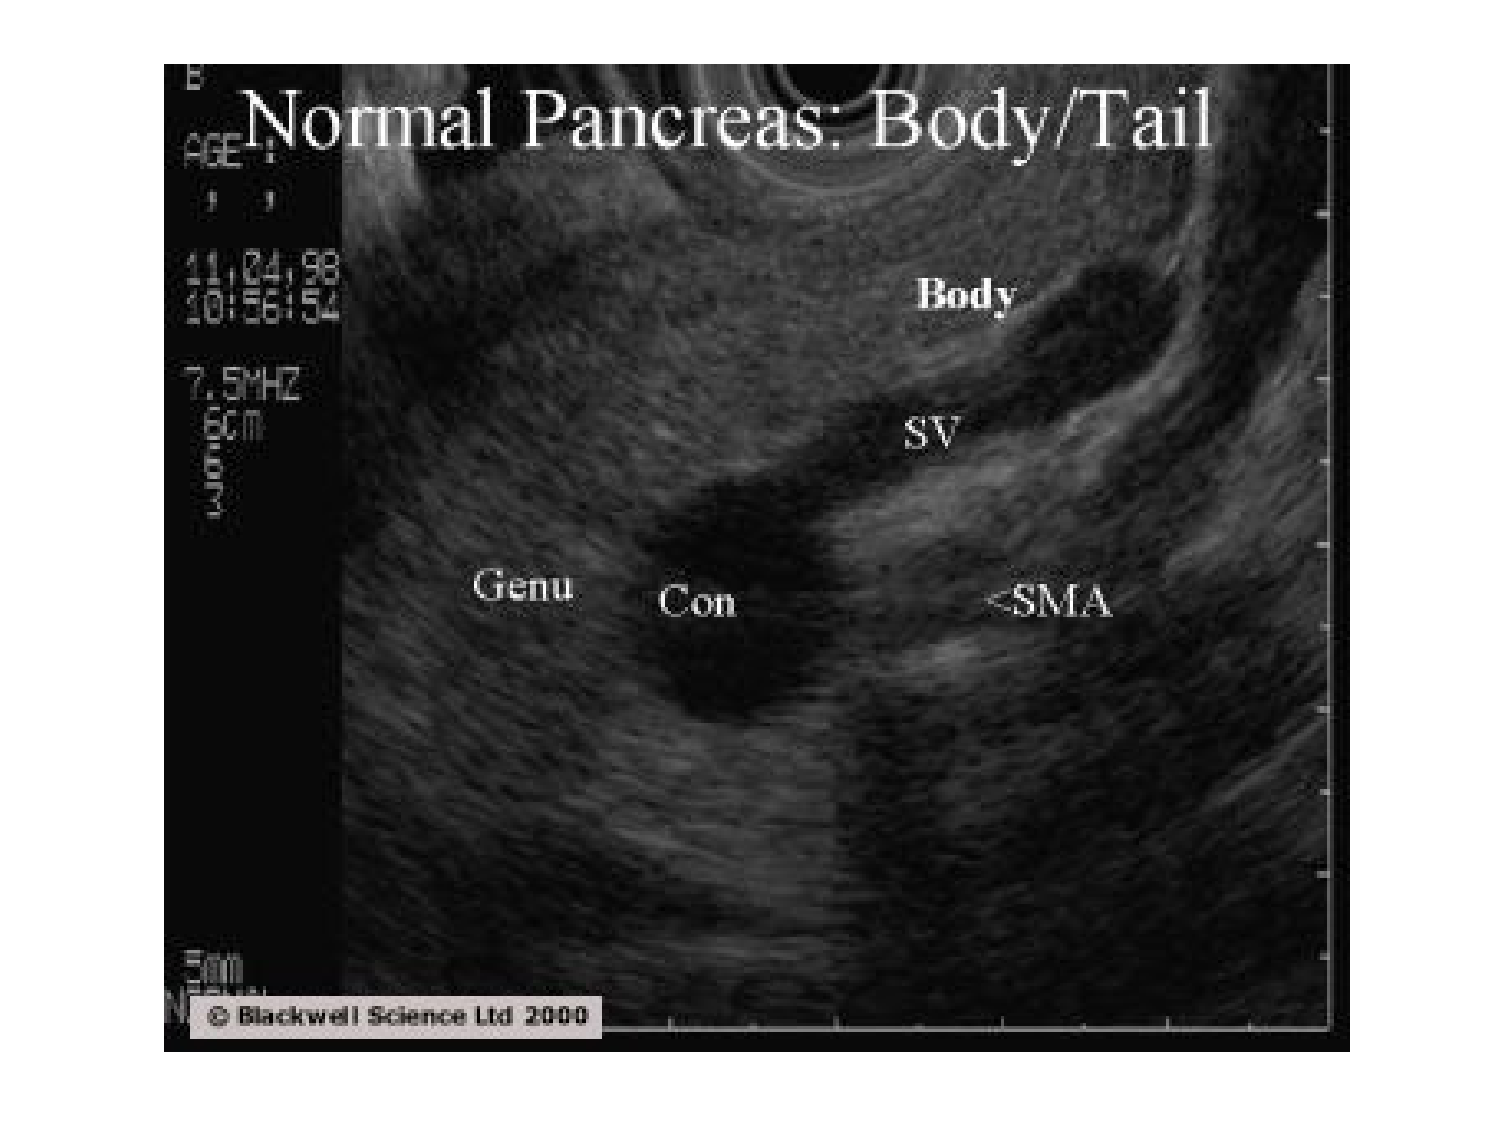

11.35 · Abdomen gros intestin foie rate pancreas vascularisation

Abdomen gros intestin foie rate pancreas vascularisation